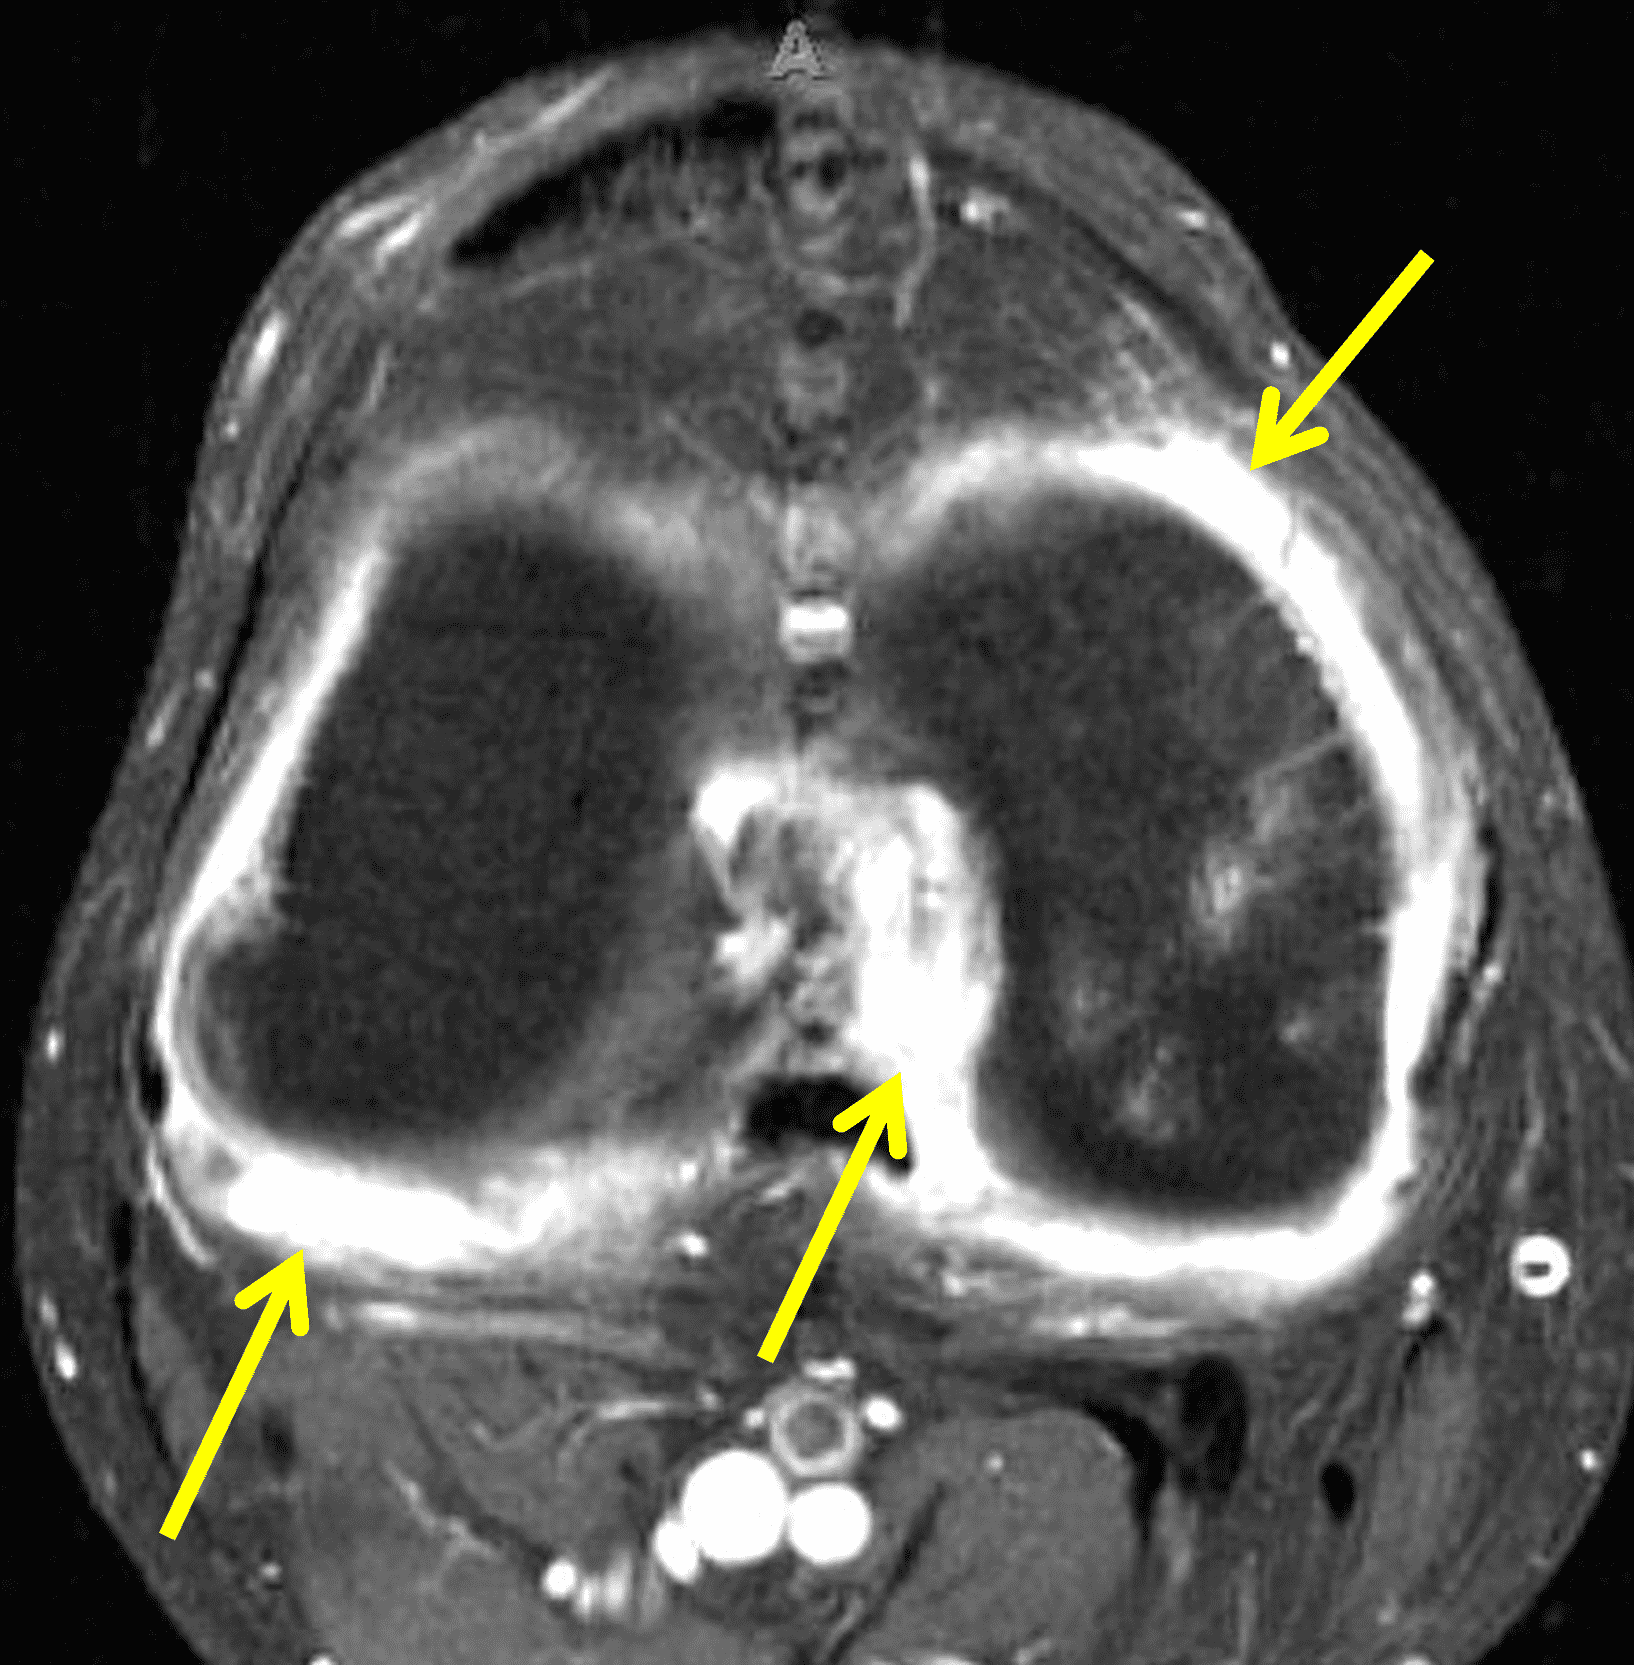

Figure 2: (2A) The coronal image shows a large effusion and severe hypertrophic synovitis (asterisks) in the knee. (2B) On the sagittal image the hypertrophic synovium (asterisks) involves the suprapatellar and infrapatellar recesses as well as the anterior and posterior intercondylar notch. A reactive lymph node (arrow) is present in the popliteal fossa. (2C) The axial image demonstrates myositis (arrows) involving the popliteus and peroneus longus muscles. Note the preserved articular cartilage, lack of erosions, and the absence of subcutaneous or marrow edema.

The causative spirochete invades the synovium, triggering a host inflammatory response that leads to synovial hypertrophy and inflammation, resulting in the characteristic clinical symptoms and imaging findings associated with Lyme arthritis.2 Common MR findings associated with Lyme arthritis include synovitis, joint effusion, popliteal lymphadenopathy, and myositis predominantly involving the popliteus (Figure 4).2,3,9 In contrast to acute septic arthritis due to more common bacteria, subcutaneous edema, marrow edema, erosions, and osteomyelitis are uncommon (Figure 4C).

Figure 4: Lyme arthritis. Fat-suppressed, fluid-sensitive images. (4A) Transverse image shows severe proliferative synovitis in the anterior and posterior joint recesses (arrows). Note the lack of surrounding subcutaneous edema. (4B) In addition to synovitis, the sagittal image shows multiple reactive lymph nodes (red arrows) and popliteal myositis (white arrow). (4C) Coronal image also shows patchy non-joint centered marrow edema in the distal femur and proximal tibia (asterisks), which is uncommon in Lyme disease compared to acute septic arthritis.

Pediatric patients often present with a more acute clinical picture including fever, difficulty weight-bearing, elevated serum inflammatory markers, and elevated synovial white blood cell count, all of which can also be seen in the setting of acute septic arthritis due to other bacteria.5,9,12 Several studies have identified MR findings that help distinguish Lyme arthritis from septic arthritis for clinical decision-making. Both groups of patients will have synovitis and an effusion related to synovial inflammation and hyperemia. However, subcutaneous edema is highly associated with septic arthritis (Figure 5) and uncommon in Lyme arthritis. Marrow edema and erosions are much more common in septic arthritis, while osteomyelitis – actual infection of the bone – only occurs septic arthritis.2,3,9 Myositis can be seen in both conditions, but severe diffuse myositis is more highly correlated with septic arthritis (Figure 5).2